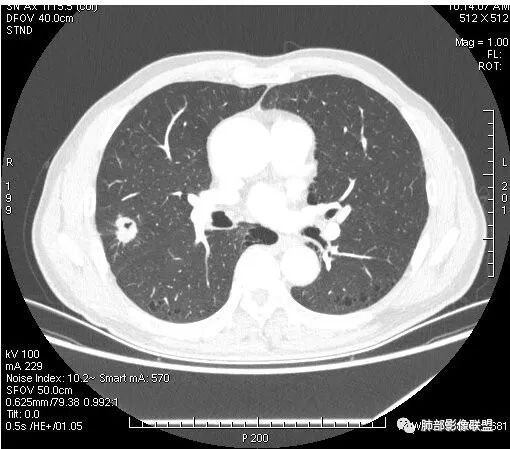

患者右上肺占位,内部强化不均,有空泡,有血管穿过,血管聚集现象,似有胸膜牵拉,考虑恶性

右肺上叶后段占位病灶,病灶不规则,周围胸膜线性牵拉,病灶部分周围有晕,病灶内见不规则空洞,未见明显引流支气管,长毛刺,多分叶、肿块边缘部分L型,可见血管直接供养。增强见点状坏死、病灶内血管。综上考虑恶性可能性大,鉴别隐球菌。

右肺上叶结节,浅分叶膨隆,边缘可见胸膜牵拉及血管集束,不规则厚壁空洞,不均匀强化,血管进入病灶,边缘毛燥,考虑低分化腺癌,鉴别隐球菌。

影像学改变:

1.右肺上叶后段类圆形结节影,密度不均,有坏死空洞,坏死比较彻底,内外壁都较清楚。

2.病灶有浅切迹,没有深分叶,毛刺大多细长且柔软。

3.可见棘状突起及胸膜牵拉,但未见胸膜凹陷。

什么意思?结节影有牵拉的动作,但似乎“出工不出力”,收缩力羸弱!

4.病灶轻到中度强化。病灶内血管走行较完好,病灶旁血管局部显示粗大。

5.支气管关系不确定。

6.灶周见小结节影(卫星灶),边界不甚清晰。